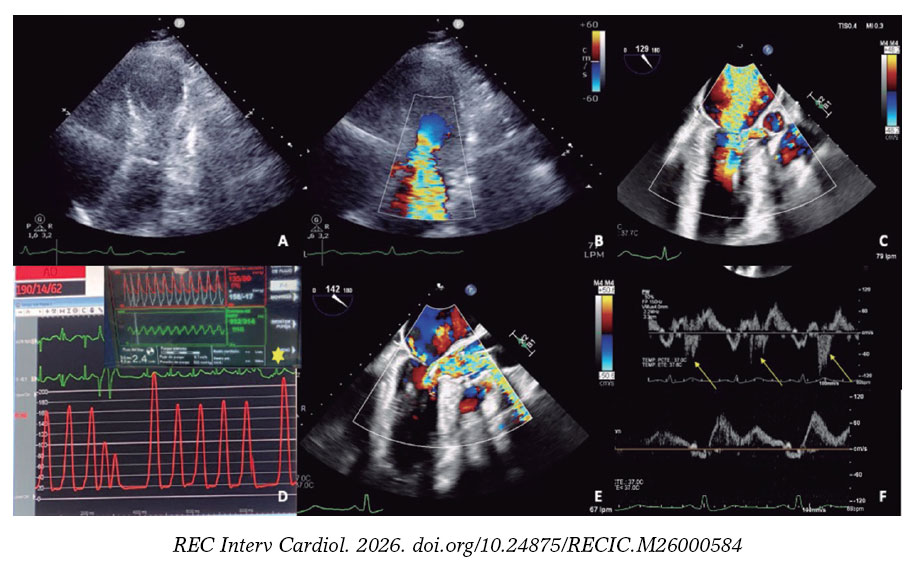

El implante del dispositivo Imp ella-CP (figura 1D, asterisco) ajustando un flujo de 2,4 l/min (P4) para evitar la succión, produjo una mejora hemodinámica y respiratoria inmediata, con disminución de la insuficiencia mitral (figura 1E,F, flechas: onda S sistólica). Una segunda rama septal (RS) mostraba compresión extrínseca, y se seleccionó tras confirmar la irrigación septal (figura 2A, flecha: segunda RS; asterisco: primera RS). Se implantaron 2 coils (figura 2B) por la potencial reversibilidad, con reducción inmediata del flujo y reducción de ODTSVI.

Tras 24 horas, la situación hemodinámica se deterioró. Debido a una ligera elevación de las enzimas cardiacas y una reaparición de ODTSVI, se realizó ablación con alcohol de la segunda RS. Dado que persistía la contractilidad más basal del septo (figura 2C, óvalo), se decidió ocluir también la primera RS, implantando un stent farmacoactivo en la descendente anterior proximal debido a la imposibilidad de una cateterización selectiva (figura 2D); tras ello, se observaron acinesia basal septal e insuficiencia mitral ligera (vídeo S2).